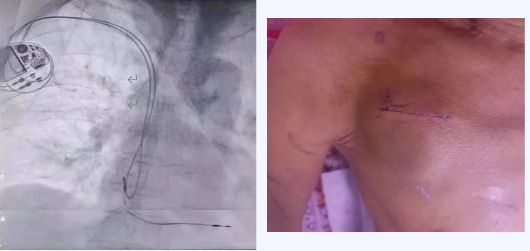

生命奇迹每天都在心内三科发生,2024年3月,蔡景景率领心内三科团队完成了一项极具挑战性的手术,为91岁的抗美援朝老兵高先生植入永久心脏起搏器,刷新了兴安盟人民医院安装永久起搏器患者的最高年龄纪录。

高先生因左下肢疼痛入院,被诊断为左下肢动脉闭塞,于血管外科接受治疗。然而,心率过慢的问题令治疗陷入僵局,蔡景景受邀前来会诊。经检查,高先生心跳每分钟仅16次到30次,同时伴有严重的胸闷、气短、乏力和反应迟钝等症状,确诊为“三度房室传导阻滞”,随时可能出现心脏骤停、恶性心律失常等致命情形。面对如此高龄且病情复杂的患者,蔡景景毫无退缩之意。经过术前评估和严密观察,她为高先生量身定制了起搏器植入的诊疗方案。手术当日,她与导管室技术团队紧密协作,在关键的1小时里,蔡景景仿若战场上的指挥官,沉着冷静地引领团队攻克一个又一个难关,最终完成手术。在医护人员的精心护理下,高先生术后恢复良好,顺利出院。